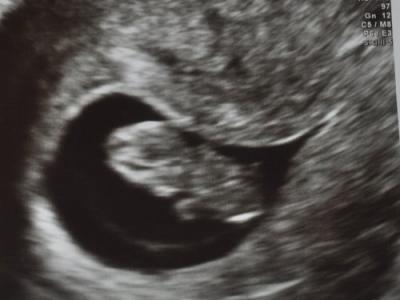

Gestern war es endlich soweit, ich durfte zum FA! Also erst bin ich zum US gegangen. Die Technikerin hat rumgeschallt und vermessen und ich habe das Baby gesehen und habe nur gebangt. ICH habe naemlich kein Herzchen blubbern sehen. Aber dann hat sie reingezoomt, alles schick. Man, war ich erleichtert! Ich habe eine besondere Gebaermutter - die ist herzfoermig. Oftmals sind damit Fruehgeburten verbunden. Ich habe auch schon zwei Fruehchen daheim und ein "Reifchen" (37+0!). Nunja, das Baby liegt auf der Seite, wo ich meinen Grossen bekommen habe vor 8 1/2 Jahren. Freu! Ich muss also dieses Mal nicht zum Risiko-Doc. Ich werde schon enger ueberwacht, muss ab 14. SSW Progesteronspritzen bekommen (damit die Gebaermutter besser waechst), aber ansonsten bin ich endlich mal "normal" schwanger. Die "leere" Seite hat derzeit Fluessigkeit drin, was zu Blutungen fuehren KANN. Ich hatte ja auch schon oefter SB, aber das ist normal und OK so. Naechster Termin in 5 Wochen! Nur Herztoene abhoeren und Fundusstand kontrollieren. Es wurde auch kein Blut gezapft, keine Urinprobe - und was im am Amiland besonders liebe - keine vag. Untersuchung! (Das bringt nur immer Keime und moegliche Infektionen mit sich ...) Amiland - ich wohne in Louisiana, in der Naehe von New Orleans :). Mama Angie kennt mich schon aus dem Dezi 2004 Forum *winke* ;). Hab nur ein neues Login, da ich mein altes Passwort nicht mehr wusste *huestel*. Erleichterte Gruesse, Katja